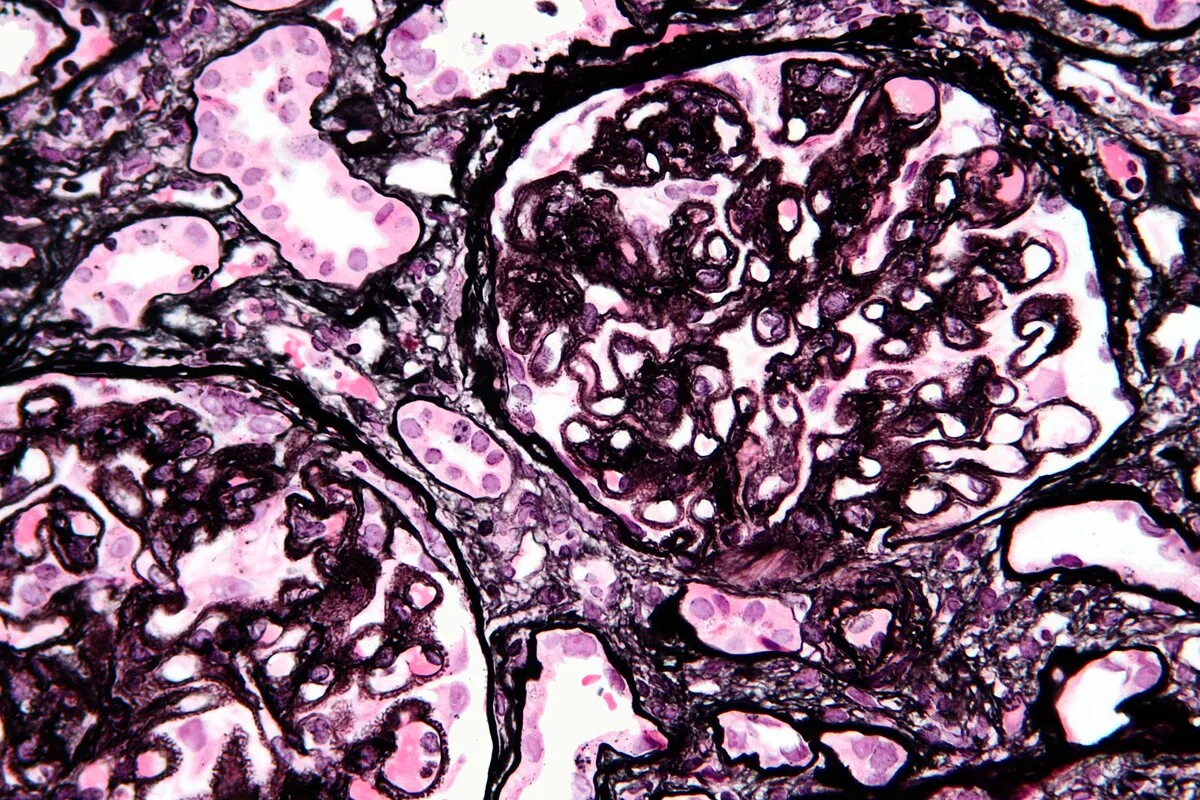

Meu paciente com NIgA tem proteinúria entre 0,5–1,0 g/dia, já está em iECA e iSGLT2: devo pensar em imunossupressão?

Proteinúria entre 0,5–1,0 g/dia na NIgA não é benigna e já se associa a maior risco de progressão renal. A evidência atual reforça <0,5 g/dia como alvo terapêutico, valorizando proteinúria cumulativa e tendência ao longo do tempo. Antes de pensar em imunossupressão, o foco deve ser otimização máxima da terapia de suporte e estratificação cuidadosa de risco.